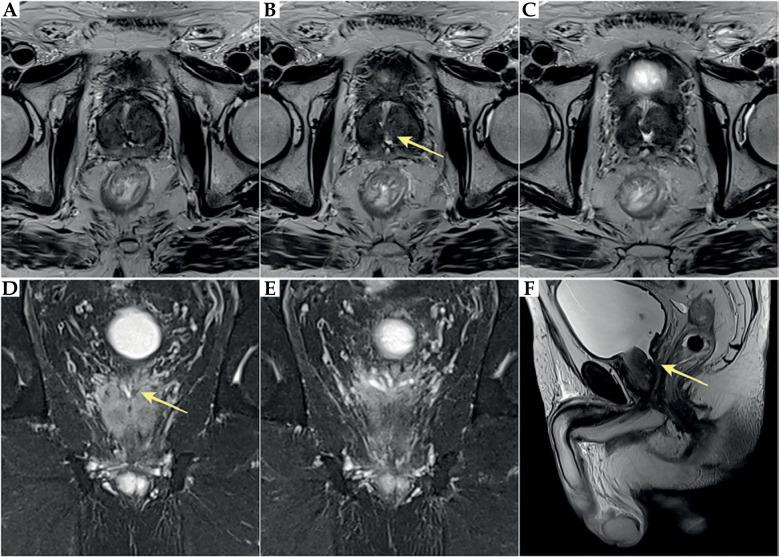

The aim of this paper was to present a rare complication of orchiepididymitis in a patient treated with brachytherapy (BT) for prostate cancer, who underwent trans-ureteral resection of the prostate (TURP) four weeks after BT. A 73-year-old patient with prostate cancer (intermediate-risk group) was eligible for high-dose-rate (HDR) BT combined with androgen deprivation therapy (ADT) for 6 months (leuprorelin). Due to increased symptoms, such as urinary retention after BT, the patient required catheterization. Additionally, bacterial inflammation in the lower urinary tract and prostate was present. Due to prolonged micturition disorders, TURP was performed, leading to chronic orchiepididymitis four months after completion of BT and three months after catheter removal following TURP. Due to long-term inflammation, which was resistant to treatment, the left testicle with left epididymis was removed. Unfortunately, inflammatory symptoms occurred post-operatively in the bed and the left groin. Since these symptoms of varying severity continued, anti-inflammatory drugs and analgesics were introduced. TURP performed too quickly after HDR-BT might cause severe complications. Extreme caution regarding TURP should be exercised in patients undergoing BT. Conservative and pharmacological treatment must be introduced in the occurrence of urinary disorders after BT, and any intervention (TURP) should be performed at least 3-6 months after BT. This is especially crucial because of the development of radiation effect over time.

本文的目的是介绍一名接受前列腺癌近距离放射治疗(BT)的患者发生的罕见附睾炎并发症,该患者在BT治疗四周后接受了经尿道前列腺切除术(TURP)。一名73岁的前列腺癌患者(中危组)符合接受高剂量率(HDR)BT联合雄激素剥夺治疗(ADT)6个月(亮丙瑞林)的条件。由于BT后出现诸如尿潴留等症状加重,患者需要导尿。此外,下尿路和前列腺存在细菌感染。由于排尿障碍持续存在,患者接受了TURP,导致在BT完成四个月后以及TURP后拔除导尿管三个月后发生慢性附睾炎。由于长期炎症对治疗有抵抗性,切除了左侧睾丸及附睾。不幸的是,术后在床上和左侧腹股沟出现了炎症症状。由于这些不同程度的症状持续存在,开始使用抗炎药和镇痛药。HDR-BT后过快进行TURP可能会导致严重并发症。接受BT的患者在进行TURP时应极其谨慎。BT后出现排尿障碍时必须采取保守和药物治疗,任何干预措施(TURP)应在BT后至少3至6个月进行。由于放射效应会随时间发展,这一点尤为关键。